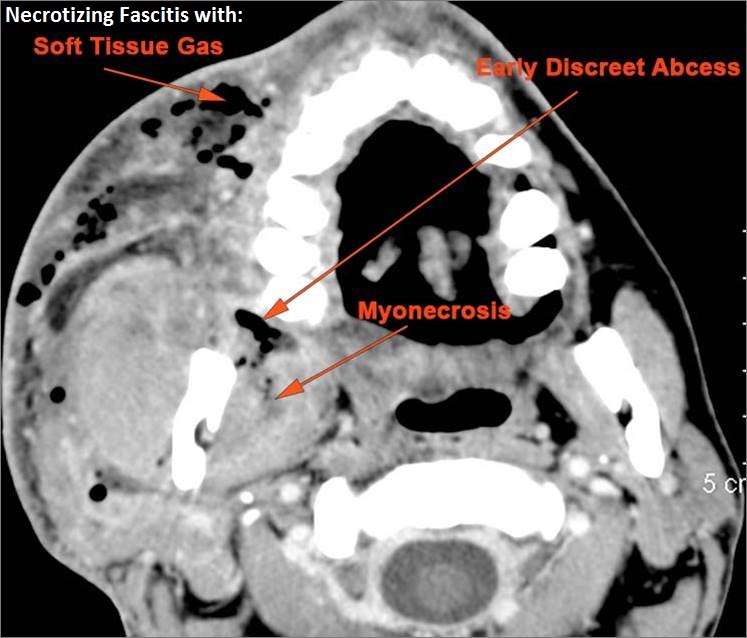

There is significant secondary airway encroachment present.

There is edema (cellulitis) and/or abscess within the fat surrounding the parotid gland and/or of the masticator space or other adjacent spaces.

There is evidence of thrombus, thrombophlebitis or other occlusive or inflammatory process of the jugular vein or smaller venous tributaries.

Other significant abnormal findings are present.